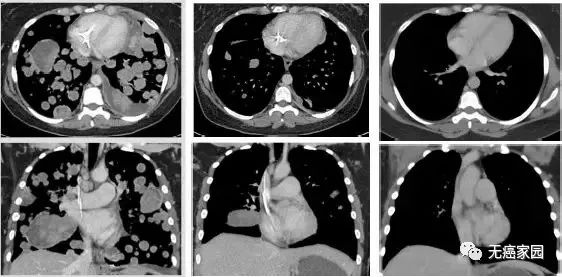

她的医生重新检查了对她的肿瘤样本进行的下一代基因组测试的结果。他们发现她的肿瘤有一个罕见的突变,称为NTRK基因融合。次年3月,Miller的病情严重到肿瘤充满90%的肺部,幸运的是她能够成为首位接受这种融合治疗的患者。

在开始每天两次服用拉罗替尼的3天内,Miller可以坐起来并且完整地讲话;

一个月后,她呼吸完全正常了;

到了6个星期,她可以骑马了,情况一直都在不断地好转。

现在,她的随访扫描结果显示,在过去三年她都已经没有癌症的迹象!

图示分别为治疗前、治疗3周期第1天、治疗13周期第1天